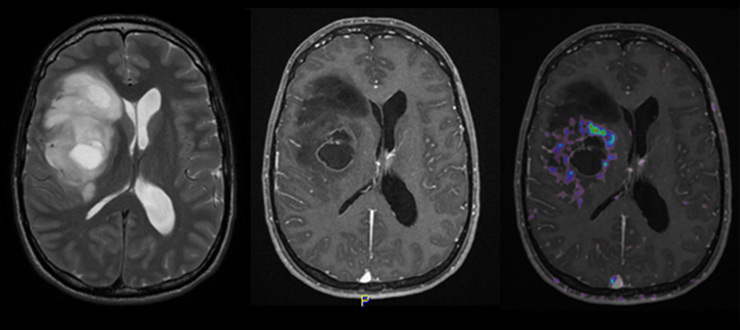

At the present time, screening for gliomas has no clinical relevance. This is because of the low incidence, the lack of sensitive biomarkers in plasma, and the observation that gliomas may develop apparently de novo within few weeks or months. Thus, the diagnosis is mainly based on neuroimaging in individuals suspected of harbouring an intracranial lesion which is performed because of clinical history (e.g. seizure, personality change or neurological deficits) confirmed by neurological examination or encephalography (EEG). Magnetic resonance imaging (MRI) is the method of choice to rule out or detect an intracranial neoplasm (figure 1). The diagnosis, treatment and follow-up of patients with malignant gliomas is an interdisciplinary challenge that is best met by specialised centres with dedicated brain tumour boards and interdisciplinary outpatient clinics.

Figure 1

MRI features of right fronto-temporal glioblastoma: T2–weighted MRI (left), T1–weighted MRI with contrast enhancement (middle) and amino acid (18F-ethyltyrosine) PET overlay (right) (courtesy: F. Kuhn, Zurich). On the left, a multifocal, irregular lesion with prominent oedema and mass effect on the lateral ventricle is depicted. In the middle, rim-like contrast enhancement around the necrotic core tumour lesion can be observed. On the right, the PET signal reflects hyper-metabolic areas around this necrotic lesion.

The role of other imaging modalities, including single photon emission-computed tomography (SPECT), positron emission tomography (PET), MR spectroscopy and functional MRI is currently being explored. In particular, amino acid PET is increasingly being used to identify hot spots indicative of malignant foci within extensive lesions and to define target volumes for radiotherapy.